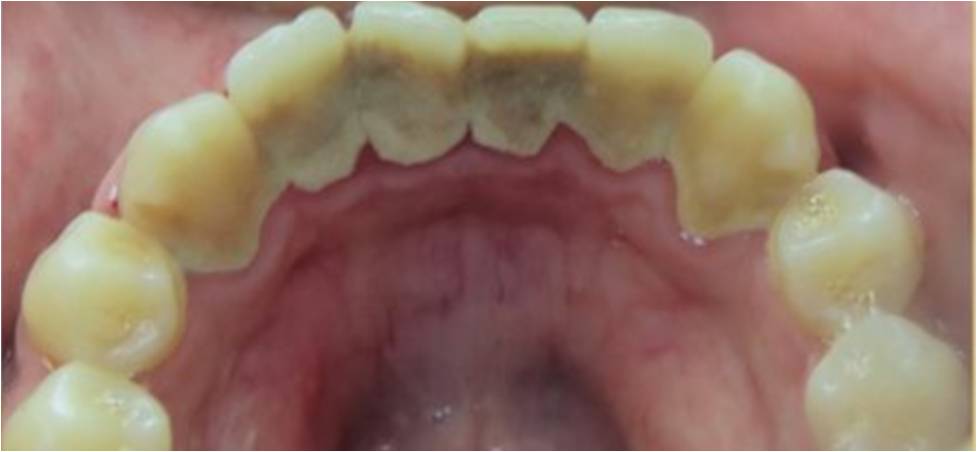

Yes. Even if you’re already very mindful of issues like gingivitis (gum inflammation), you brush and floss twice daily to so there’s no food particles stuck between your teeth, and you use a fluoride mouthwash regularly, you simply can’t carry out a “deep clean” (including below the gumline) like a professional can. The process involves thorough plaque and tartar removal using an instrument called a scaler, followed by treatment with a high-powered electric brush and special toothpaste, and professional flossing to dislodge any hard-to-reach debris and plaque.

Your teeth will certainly look brighter and whiter after a deep clean, because tartar build-up takes on a yellowish hue. As the removal of plaque and tartar is a primary focus of the procedure, it will have an immediate positive effect on the overall look of your smile. However, if you’re looking for markedly whiter results you’ll need to book in for a whitening treatment in order to achieve them. Tooth whitening is one of the easiest and most popular cosmetic dentistry procedures we offer, and the results can be nothing short of dramatic.

Your teeth may, indeed, feel a little looser after having a deep clean, but this is definitely nothing to worry about. When the build-up of plaque and tartar is removed from in between individual teeth, naturally there is a space where it has been accommodated – in some cases, a heavy buildup has been gathering over a long period of time. The feeling of looseness shouldn’t be seen as a problem, however, and while it might take a little getting used to, it’s actually a sign the procedure has been of benefit.